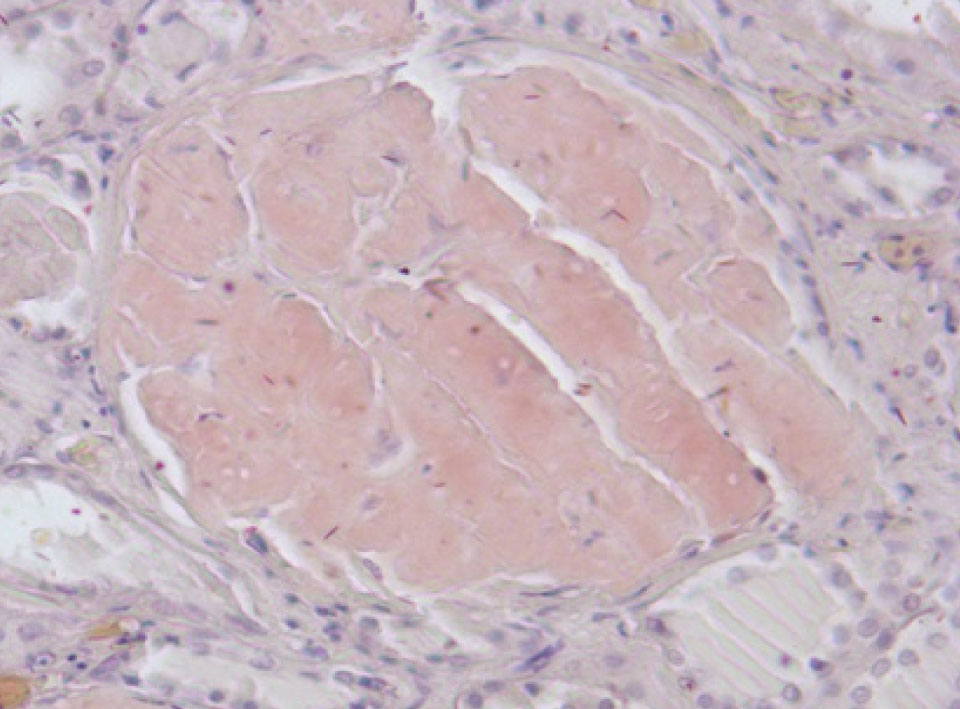

Почки – резкое уменьшение числа клубочков, отдельные полностью замещены однородной массой, дающей положительную реакцию на амилоид (рис. 3). В стенке сосудов также видны отложения амилоида (рис. 4).

Рис. 3. Почечный клубочек замещен амилоидными массами. Окраска конго красный, ×400